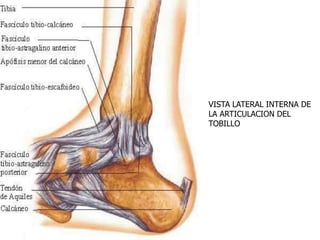

VISTA LATERAL INTERNA DE

LA ARTICULACION DEL

TOBILLO

 La estabilidad de la articulación viene dada

por la configuración de la mortaja y por los

ligamentos, de los que hay tres grupos:

A- ligamentos de la sindesmosis:

constituidos por el ligamento tibioperoneo

anterior, el ligamento tibioperoneo

posterior, el ligamento transverso inferior y

el ligamento interóseo.

B- ligamentos del complejo lateral externo.

C- ligamento lateral interno es el deltoideo

con sus dos fascículos superficial y

profundo.